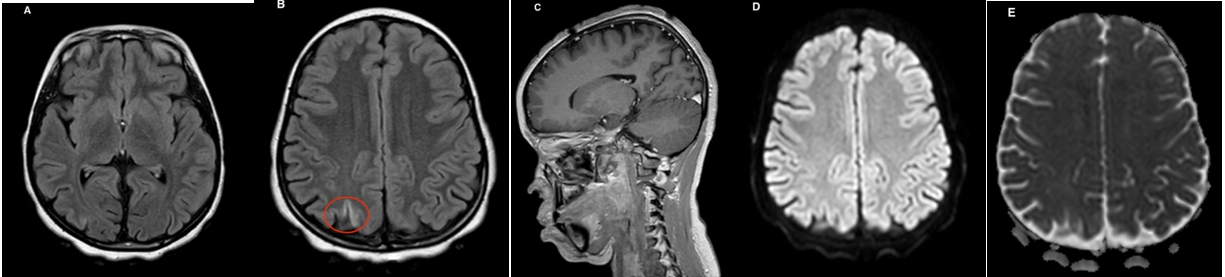

After a nephro-pediatric opinion, it was decided to continue corticosteroids and a dose of rituximab at 375 mg/m2 (if Absence of proteinuria and Ig anti-VZV positive). At the end of his hospitalization, blood pressure normalized with a good biological clinico evolution. Brain magnetic resonance imaging 6 months later to show a regression of lesions (Figure 2 - 2).

Figure 2 – 2: A brain MRI control at 6 months in axial FLAIR (A and B), DWI with ADC mapping (D and E) and sagittal T1 FFE after injection of gadolinium (C) shows a clear regression of the parieto-occipital lesions, and persistence of a small right parietal hyper intense in FLAIR (red circle).

MRI monitoring of brain injuries is crucial, not only to confirm the diagnosis of PRES, but also to assess the effectiveness of treatment.

The MRI scatter sequence is the best diagnostic tool, and lesions appear as diffuse posterior hyperintensities of white matter in T2, FLAIR sequences and hyper intense in scatter, with a high ADC coefficient. The treatment strategy concerns early diagnosis and general measures to correct the underlying cause of PRES.